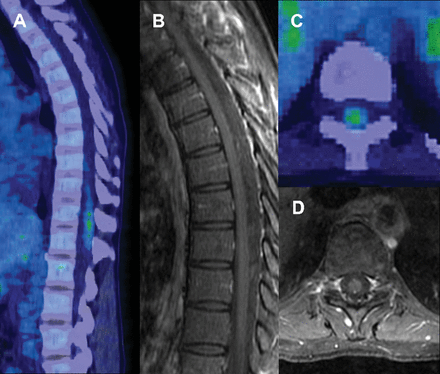

健康的43岁的女人面对bandlike腹部压力和尿频。神经系统检查是正常的。胸部CT显示纵隔腺病正与相关代谢亢进;活检证实noncaseating肉芽肿与结节病一致。脊髓被怀疑参与,因为摄影活动T9-T12 (图、A和C)和确认与脑脊液淋巴细胞脑脊液细胞增多(26细胞/μL)。Gadolinium-enhanced胸腰椎脊髓MRI是正常的(图B和D;T2图中未显示);大脑MRI没有获得。首选的影像学方法对神经gadolinium-enhanced MRI。1正信号没有MRI关联在这种情况下表明正可能提供一个更敏感的神经肉瘤的早期测试。2